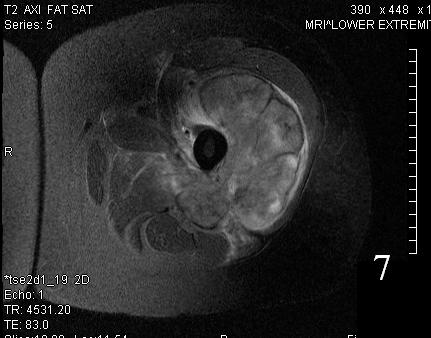

Fig. 7

Fig. 8

Fig. 7-8 Axial (Fig. 7) and coronal (Fig. 8) T2W shows heterogenous high signal intensity